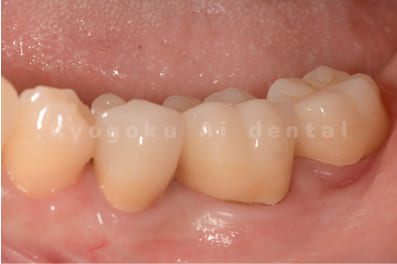

Case07

- 重度カリエス

- 治療日数

- 約3ヶ月

- 治療内容

- クラウンレングスニング、ジルコニアクラウン

- 治療費用

- 214,500円

他院で抜歯と診断された患者様です。十分な説明の下、歯を保存するクラウンレングスニングとジルコニアクラウンでの治療を行いました。治療後も問題なく経過しております。